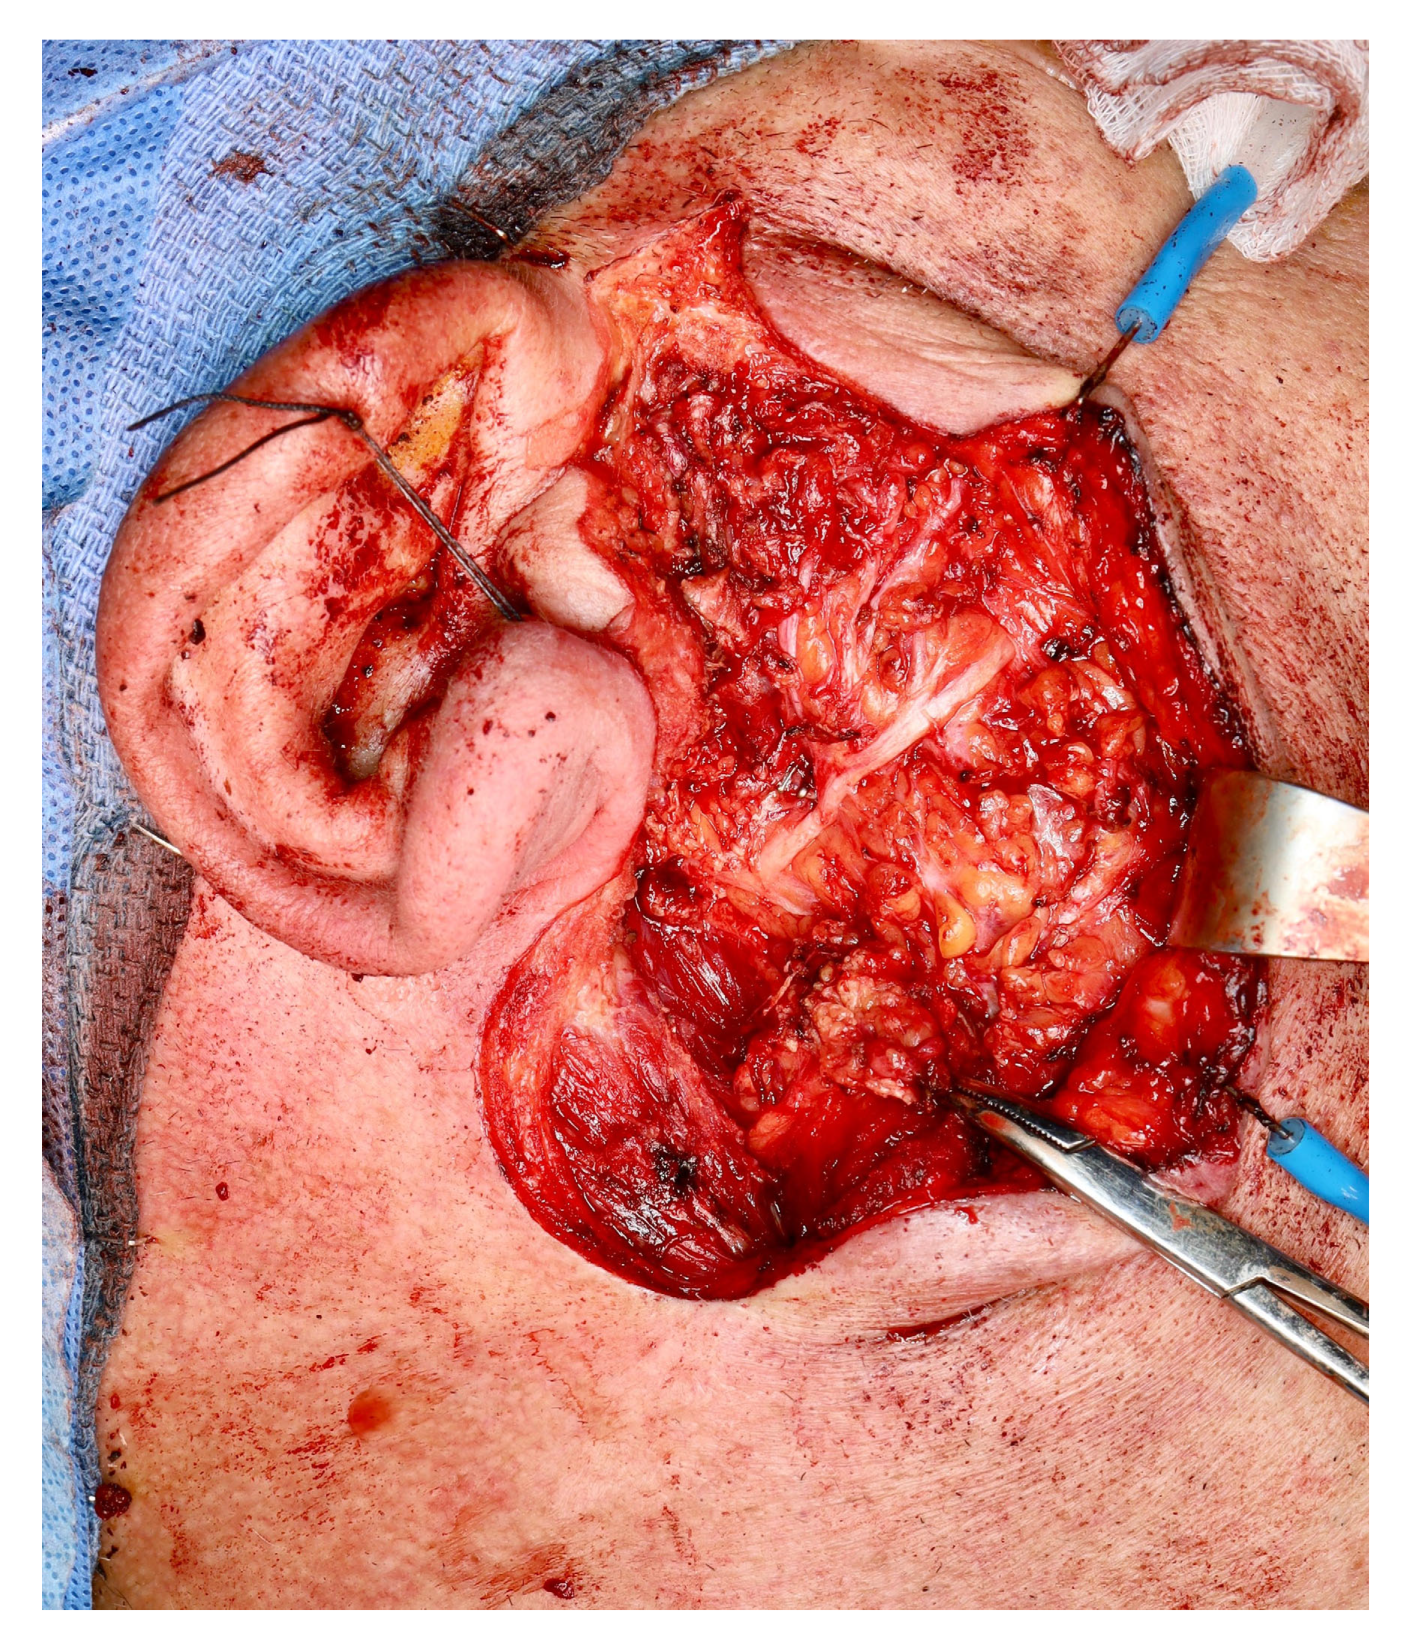

| Current case | 64 | M | Right parotid | WT | Follicular lymphoma/grade 1–2 |